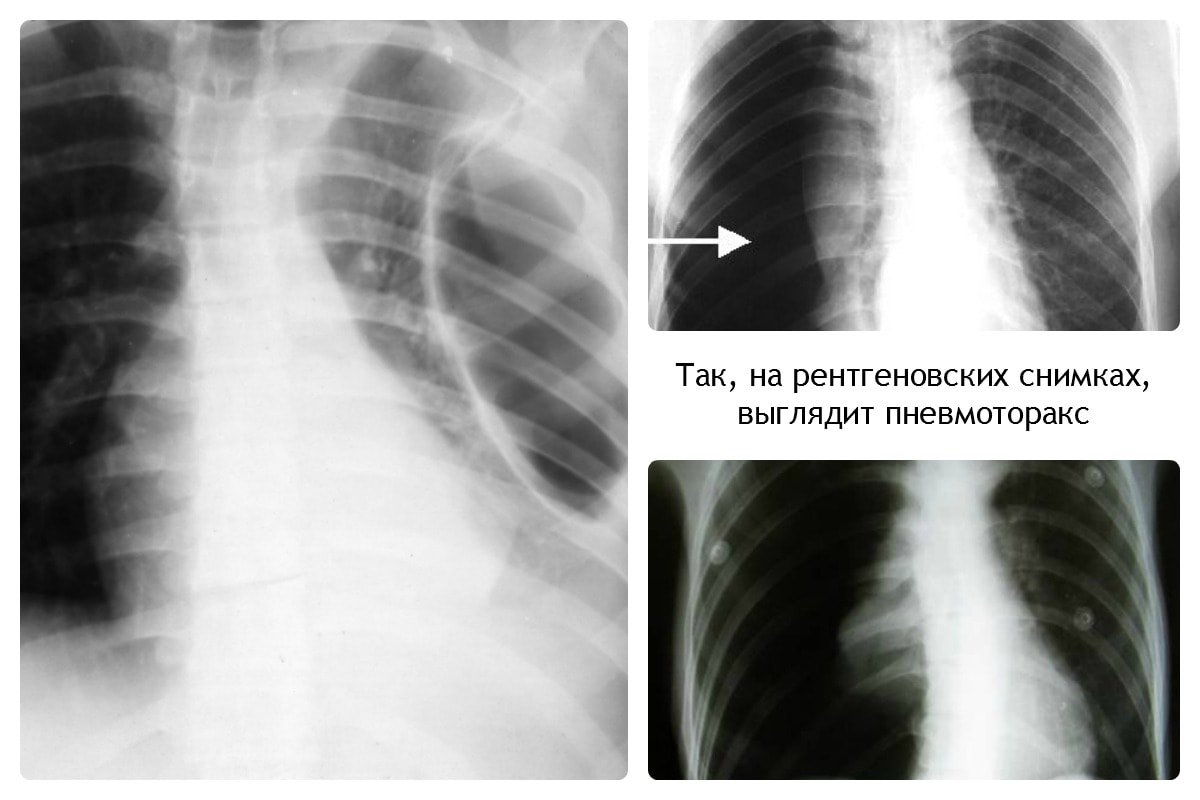

При пневмотораксе присутствует характерный уровень жидкости. На снимке отображается как просветление, лёгочный рисунок не просматривается.

Пневмоторакс